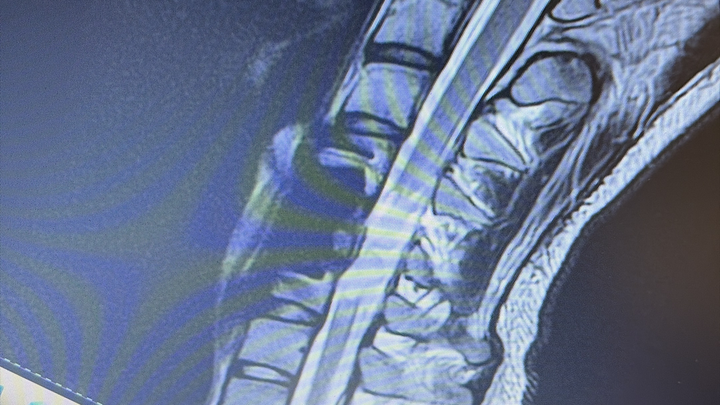

La caduta mi ha provocato la frattura delle vertebre cervicali C5-C6 portandomi a vivere la mia vita in carrozzina.

Dopo 40 giorni di rianimazione e vari interventi inizio il percorso riabilitativo, ora c’è una nuova possibilità: un intervento chirurgico per la rigenerazione del midollo spinale.

The fall caused me to break the C5 and C6 cervical vertebrae, now I live in a wheelchair. I have 70% of my body paralysed with a consequential loss of physical and sensory independence.

After 40 days in the Critical Unit Care and several surgeries I started my rehabilitation journey. Now there is a new treatment: Spinal Cord Regeneration Surgery. Thus surgery has high costs that cannot be covered by the National Health System and that I cannot afford.